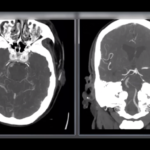

basilar artery occlusion